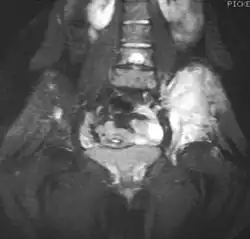

Magnetic resonance imaging (MRI) should be routinely used in the work-up of malignant tumors. It will show the full bony and soft tissue extent and relate the tumor to other nearby anatomic structures (e.g. vessels). Gadolinium contrast is not necessary as it does not give additional information over noncontrast studies, though some current researchers argue that dynamic, contrast-enhanced MRI may help determine the amount of necrosis within the tumor, thus help in determining response to treatment prior to surgery.[27]